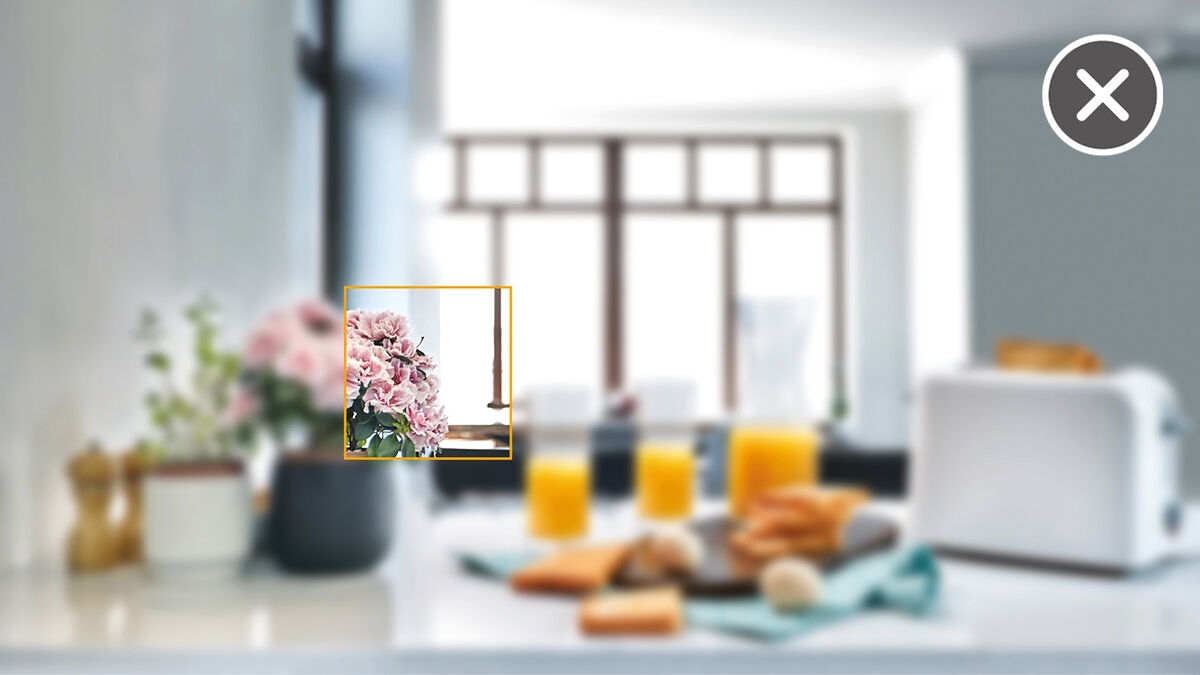

该图像显示了一张使用和不使用DCS技术的X射线图像。通过对图像的控制,亲自查看DCS传感器对图像质量的影响。

自动聚焦——无需任何手动步骤即可获得优质图像

要想拍摄高质量的全景X线照片,正确的焦距至关重要。使用自动聚焦功能,您将自动接收具有更佳对焦清晰度的图像。登士柏西诺德成像设备在一个周期内拍摄数千张单独的图像,并自动识别下颌最优定位的区域。不需要进行其他手动步骤,最终的清晰图像中就会显示这些图像。